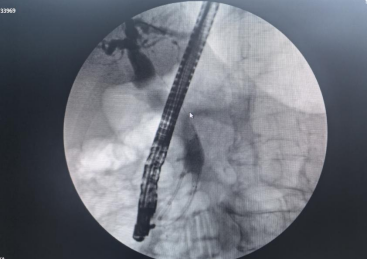

在吴文广教授的指导下,团队成功为一名56岁的胰腺癌患者实施了ERCP手术。检查提示“胰腺头颈部恶性肿瘤伴肝内外胆管及胰腺体尾部主胰管扩张”,针对患者病情,吴文广教授带领团队在术前展开充分讨论,制订了缜密的治疗方案,在与患者及家属充分沟通后最终决定通过内镜下放置胆管支架、胰管支架,为患者解除梗阻。术中,在吴文广教授的指导下,杨晨组长带领团队经预切开、插管、造影、支架置入等一系列操作,团队成功解除了胆道梗阻,最终成功引流出黑色胆汁,手术取得成功。